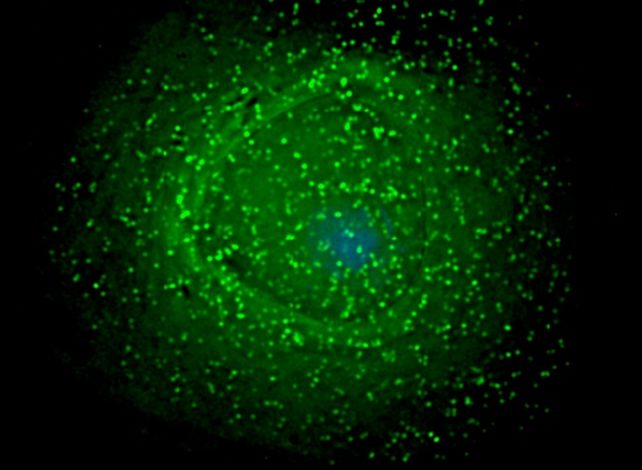

Ученые раскрыли одну из ключевых уловок вируса иммунодефицита человека (ВИЧ), которая позволяет ему десятилетиями скрываться в организме. Новое исследование проливает свет на то, где и как ВИЧ формирует свои латентные резервуары, что является важным шагом в поиске способов полного избавления пациентов от вируса. В своей скрытой стадии ВИЧ может существовать внутри определенных клеток-хозяев в виде дремлющего «провируса» — вирусного генома, встроенного в ДНК клетки человека. Именно это делает вирус таким трудным для уничтожения, даже когда современная антиретровирусная терапия подавляет его размножение и останавливает развитие болезни, но не может атаковать спрятанные провирусы.

Ранее было известно, что ВИЧ сохраняется в различных тканях, включая мозг, почки, печень, легкие и желудочно-кишечный тракт. Основным резервуаром являются Т-хелперы иммунной системы, но вирус также прячется в клетках кожи, белых кровяных тельцах и специфичных для органов клетках. Многие детали этого процесса оставались неясными. Согласно новому исследованию, ВИЧ использует тканеспецифичный подход, маскируясь в ДНК клетки-хозяина и адаптируя свое поведение в зависимости от окружения. Например, в мозге он избегает активных генов и скрывается в менее активных регионах ДНК.